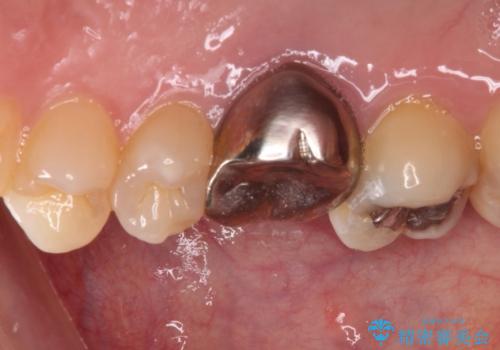

穴の空いてしまった奥歯 ゴールドインレーによるむし歯治療

- 奥歯にものが挟まって痛みがあるとのことで来院された患者様です。

目視でも分かるくらいの欠損があり、歯の内部にむし歯が進行している状態でした。

上顎奥歯で目立たないことから、ゴールドインレー(PGAインレー)による修復治療をおこなうこととしました。